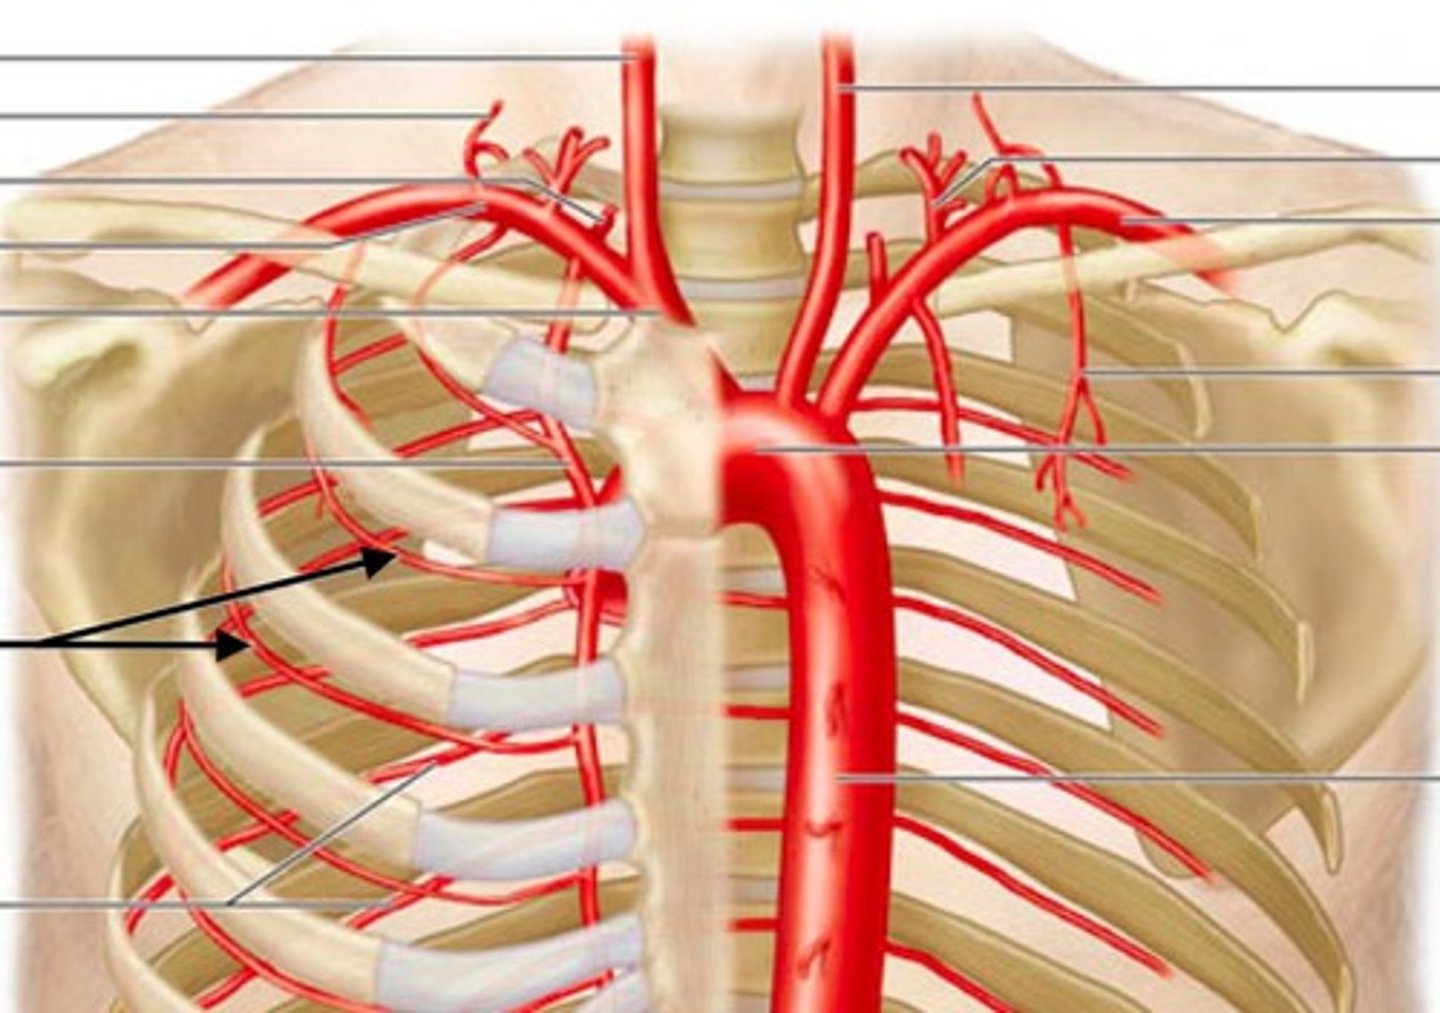

anterior intercostal arteries

What is this blood vessel?